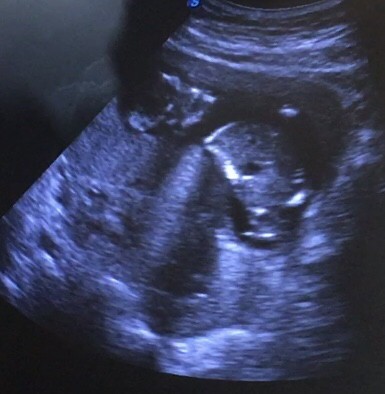

Im on my 14 weeks pregnancy po. Sumasakit sakit ung puson ko at the same time ung lower back ko is ngalay din at sumasakit at one time nanigas ang tummy ko.ngpacheck up din ako agad kinabukasan at ang sb ng OB ay okay naman si Baby. Niresetahan nya ako ng Heragest at Co Amoxiclav. Pero still ganon pdin po nararamdaman ko still may kirot padin. Anyone na experience to? Ng woworried lng po ako Okay naman si Baby bakit may pain ako nararamdaman 🥺🥺🥺